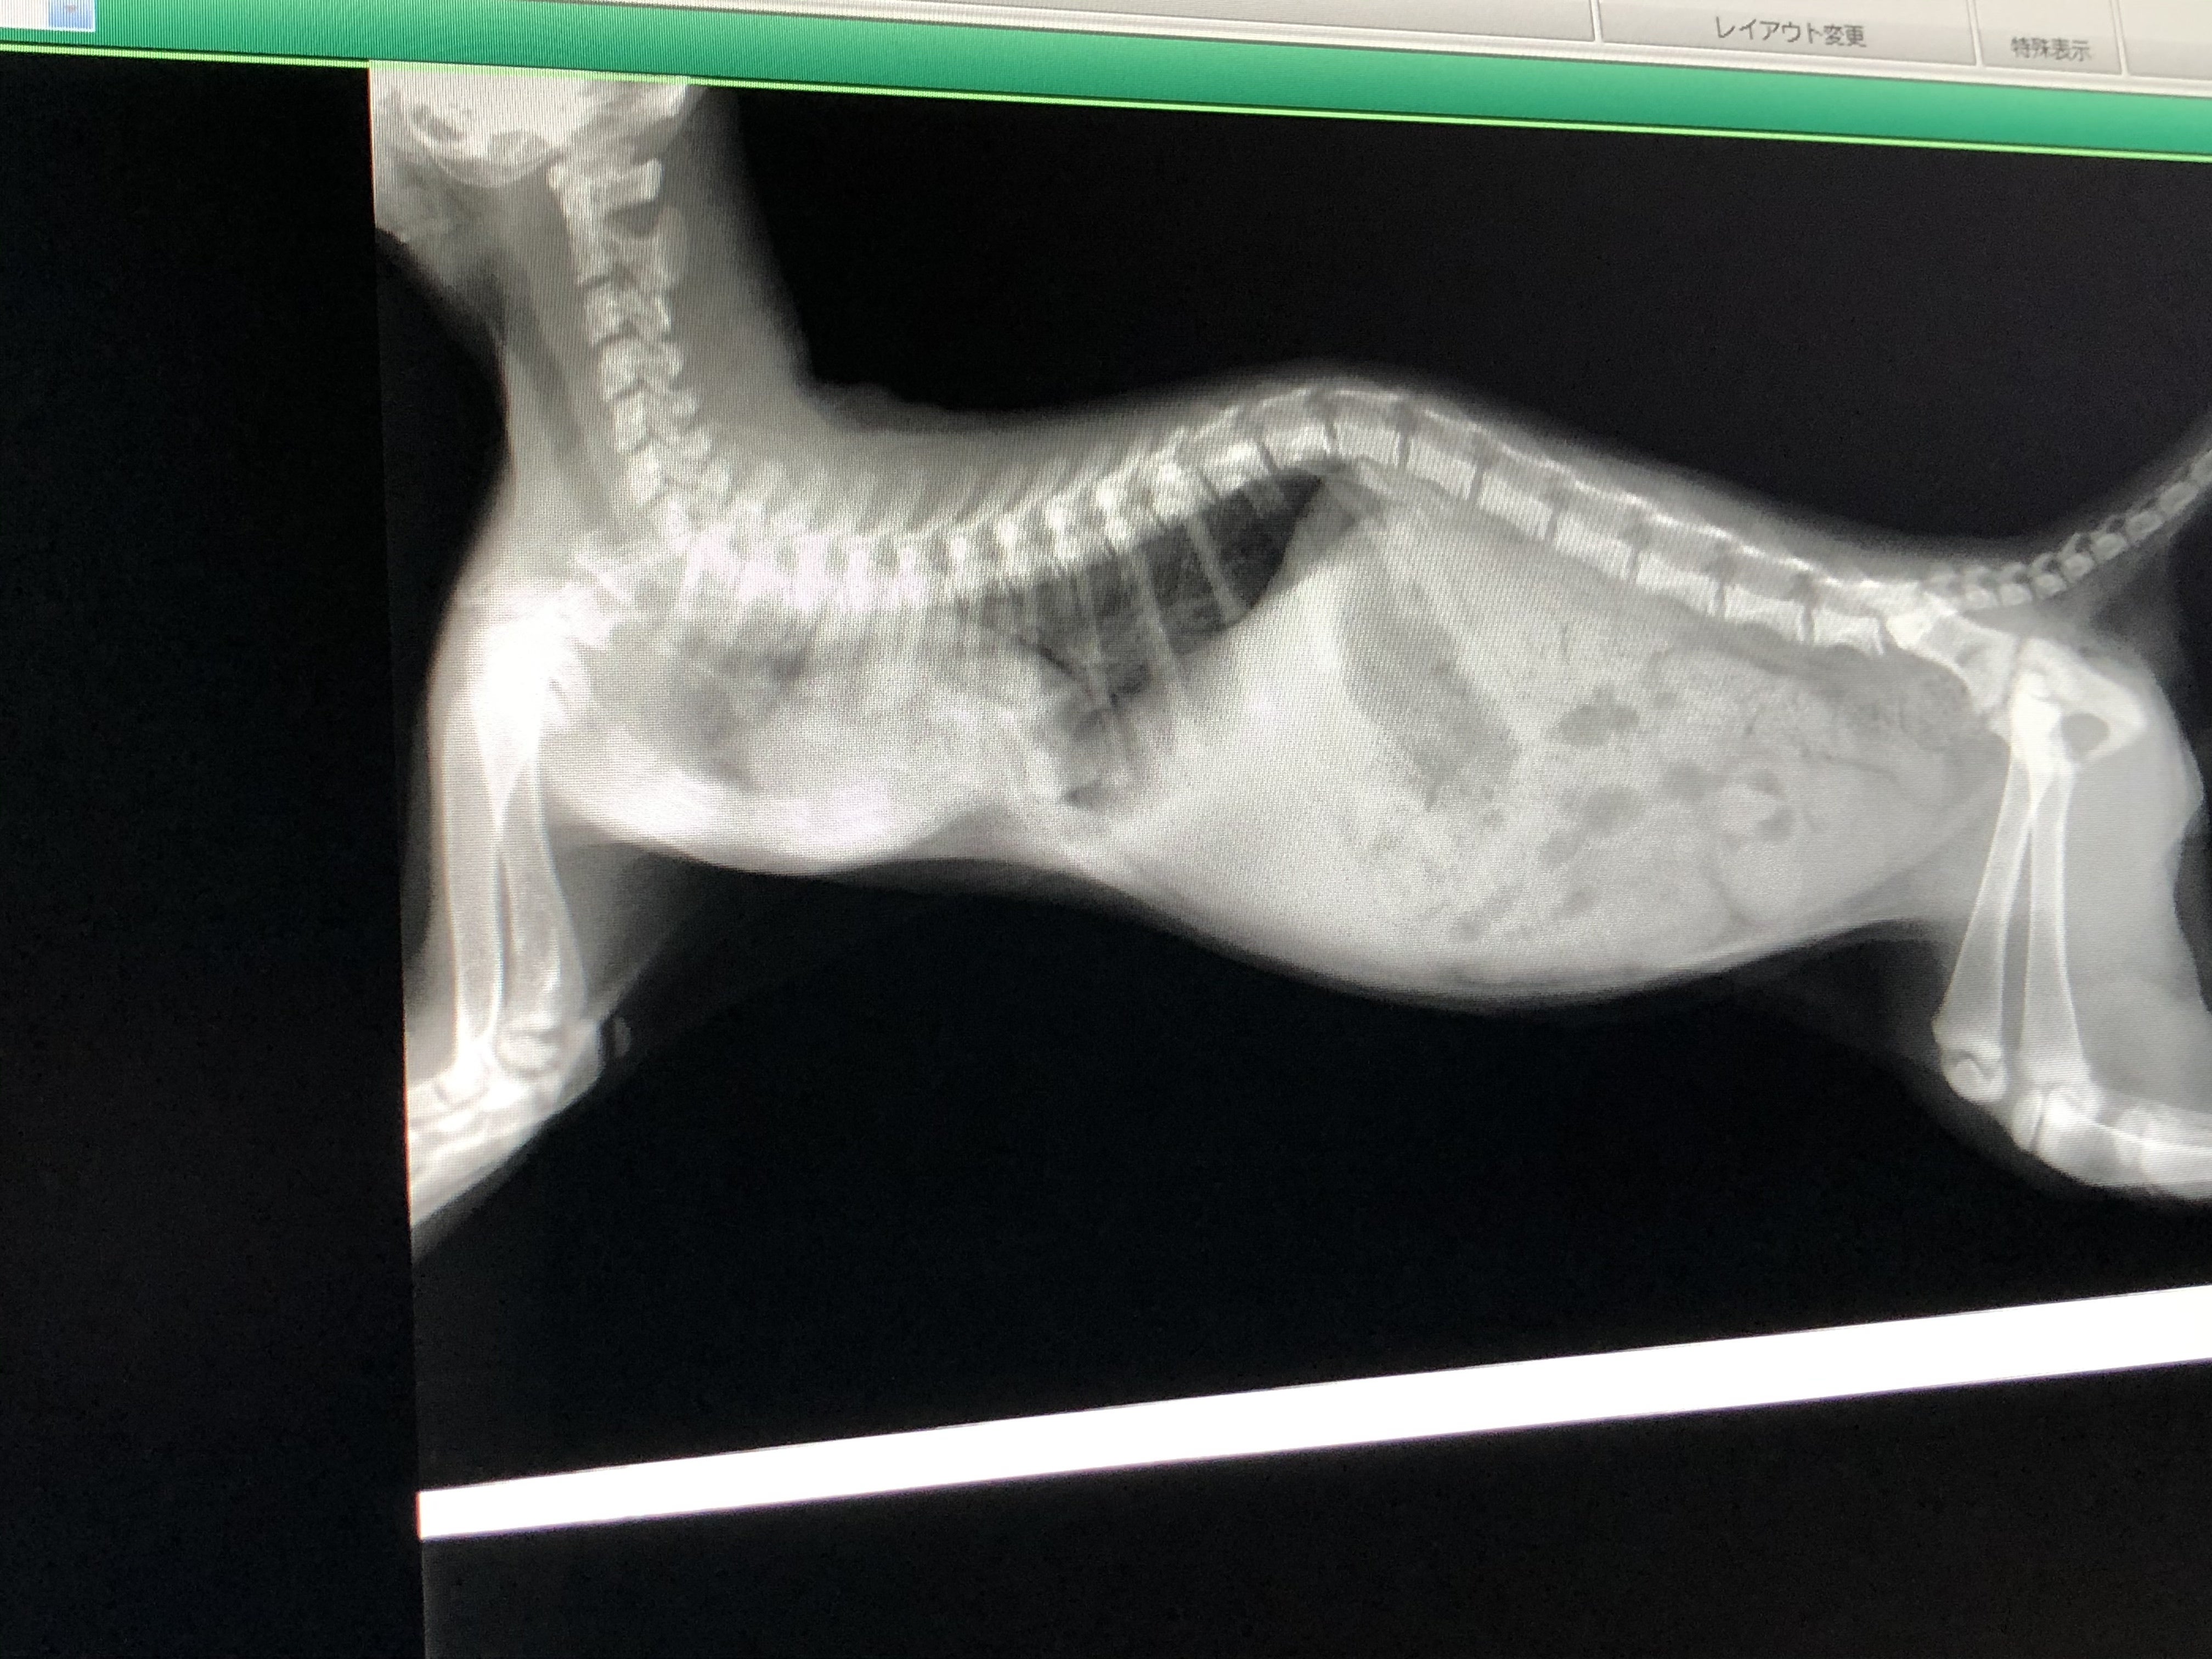

更にコロ助ちゃんは胸部肋骨が陥没している【漏斗胸】という病気を持っていました。

【漏斗胸】というのは遺伝性のある病気で、肋骨が心臓の方へ食い込んでしまい、呼吸が苦しくなってしまう病気です。

身体が成長しきる前にへこんだ胸骨を手術で引っ張る手術が必要ですが、手術に耐えるためには900gを超えなければ厳しいという診断だったので、預かりBABAさんが病気のせいもあって成長がとても遅いコロ助ちゃんに毎日せっせと高カロリー食を食べさせてくれて、ようやく手術に耐えられそうな体重になったので、先日最終検査をして2時間半を超える手術を乗り越えてくれました。